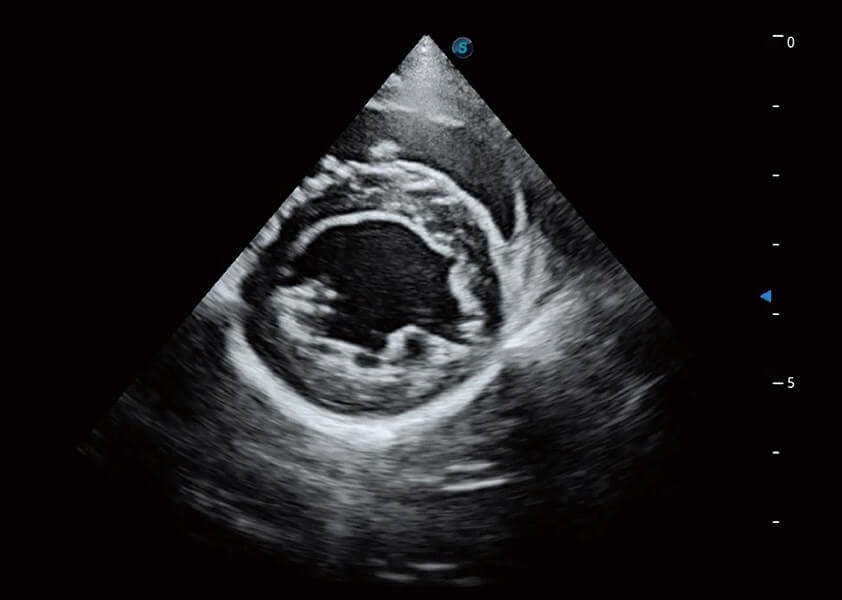

ProPet 60 作為一款高端臺(tái)式動(dòng)物超聲設(shè)備,為動(dòng)物醫(yī)生的日常診斷提供了一系列貼合動(dòng)物臨床需求、解決臨床實(shí)際問題的高級成像功能。憑借全系列高清探頭,滿足醫(yī)生對腹部、心臟、生殖、淺表、肌骨等成像的所有需求,切實(shí)幫助您提升檢查效率,提高診斷信心。